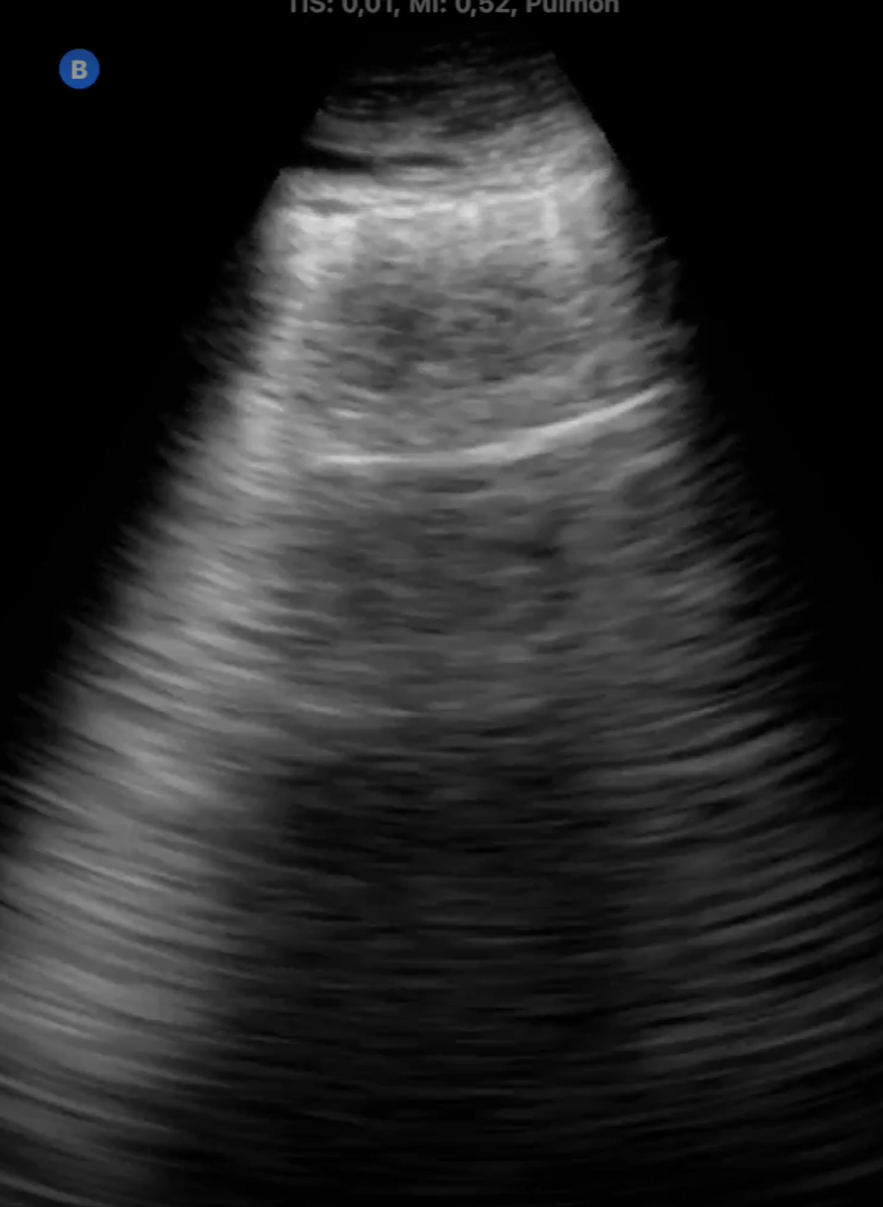

La medicina de familia no tiene horarios ni fronteras. Durante el último año, hemos incorporado el ecógrafo ultraportátil a nuestra vida diaria no como un recurso improvisado, sino como una herramienta integrada en nuestra práctica diaria capaz de dar respuesta inmediata a demandas clínicas surgidas en el entorno comunitario. En este contexto, han surgido situaciones en las que la ecografía ha sido determinante: diagnóstico de neumonías en domicilio, confirmación de roturas fibrilares tras actividad deportiva, fractura costal, valoración de hematomas y complicaciones postquirúrgicas, e incluso la identificación de una enfermedad pulmonar intersticial. Todo ello fuera del centro de salud, sin acceso a historia clínica ni a pruebas complementarias, únicamente con la sonda, la experiencia clínica… y una gran responsabilidad emocional. Estas situaciones generan un desafío distinto: no hay anonimato, y la confianza.

La ecografía ultraportátil amplía la capacidad resolutiva del médico de familia más allá de la consulta. Con herramientas sencillas y bien utilizadas, la Atención Primaria puede acercarse aún más a la población, ofrecer respuestas rápidas y mantener su esencia profundamente humana.

Cualquier médico de familia con formación básica en ecografía y acceso a un ecógrafo portátil puede implementar esta práctica. Especialmente útil en zonas rurales, en atención domiciliaria o en situaciones de difícil acceso al sistema. Reduce derivaciones innecesarias y mejora el acceso al diagnóstico precoz.